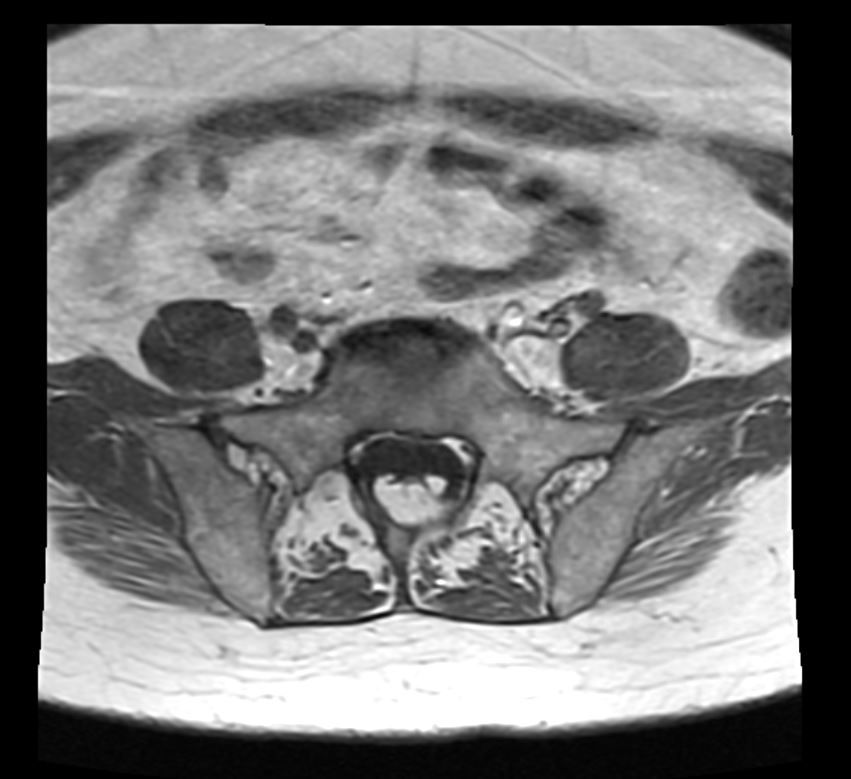

An elderly female presents with low back pain. What is the most likely imaging finding?